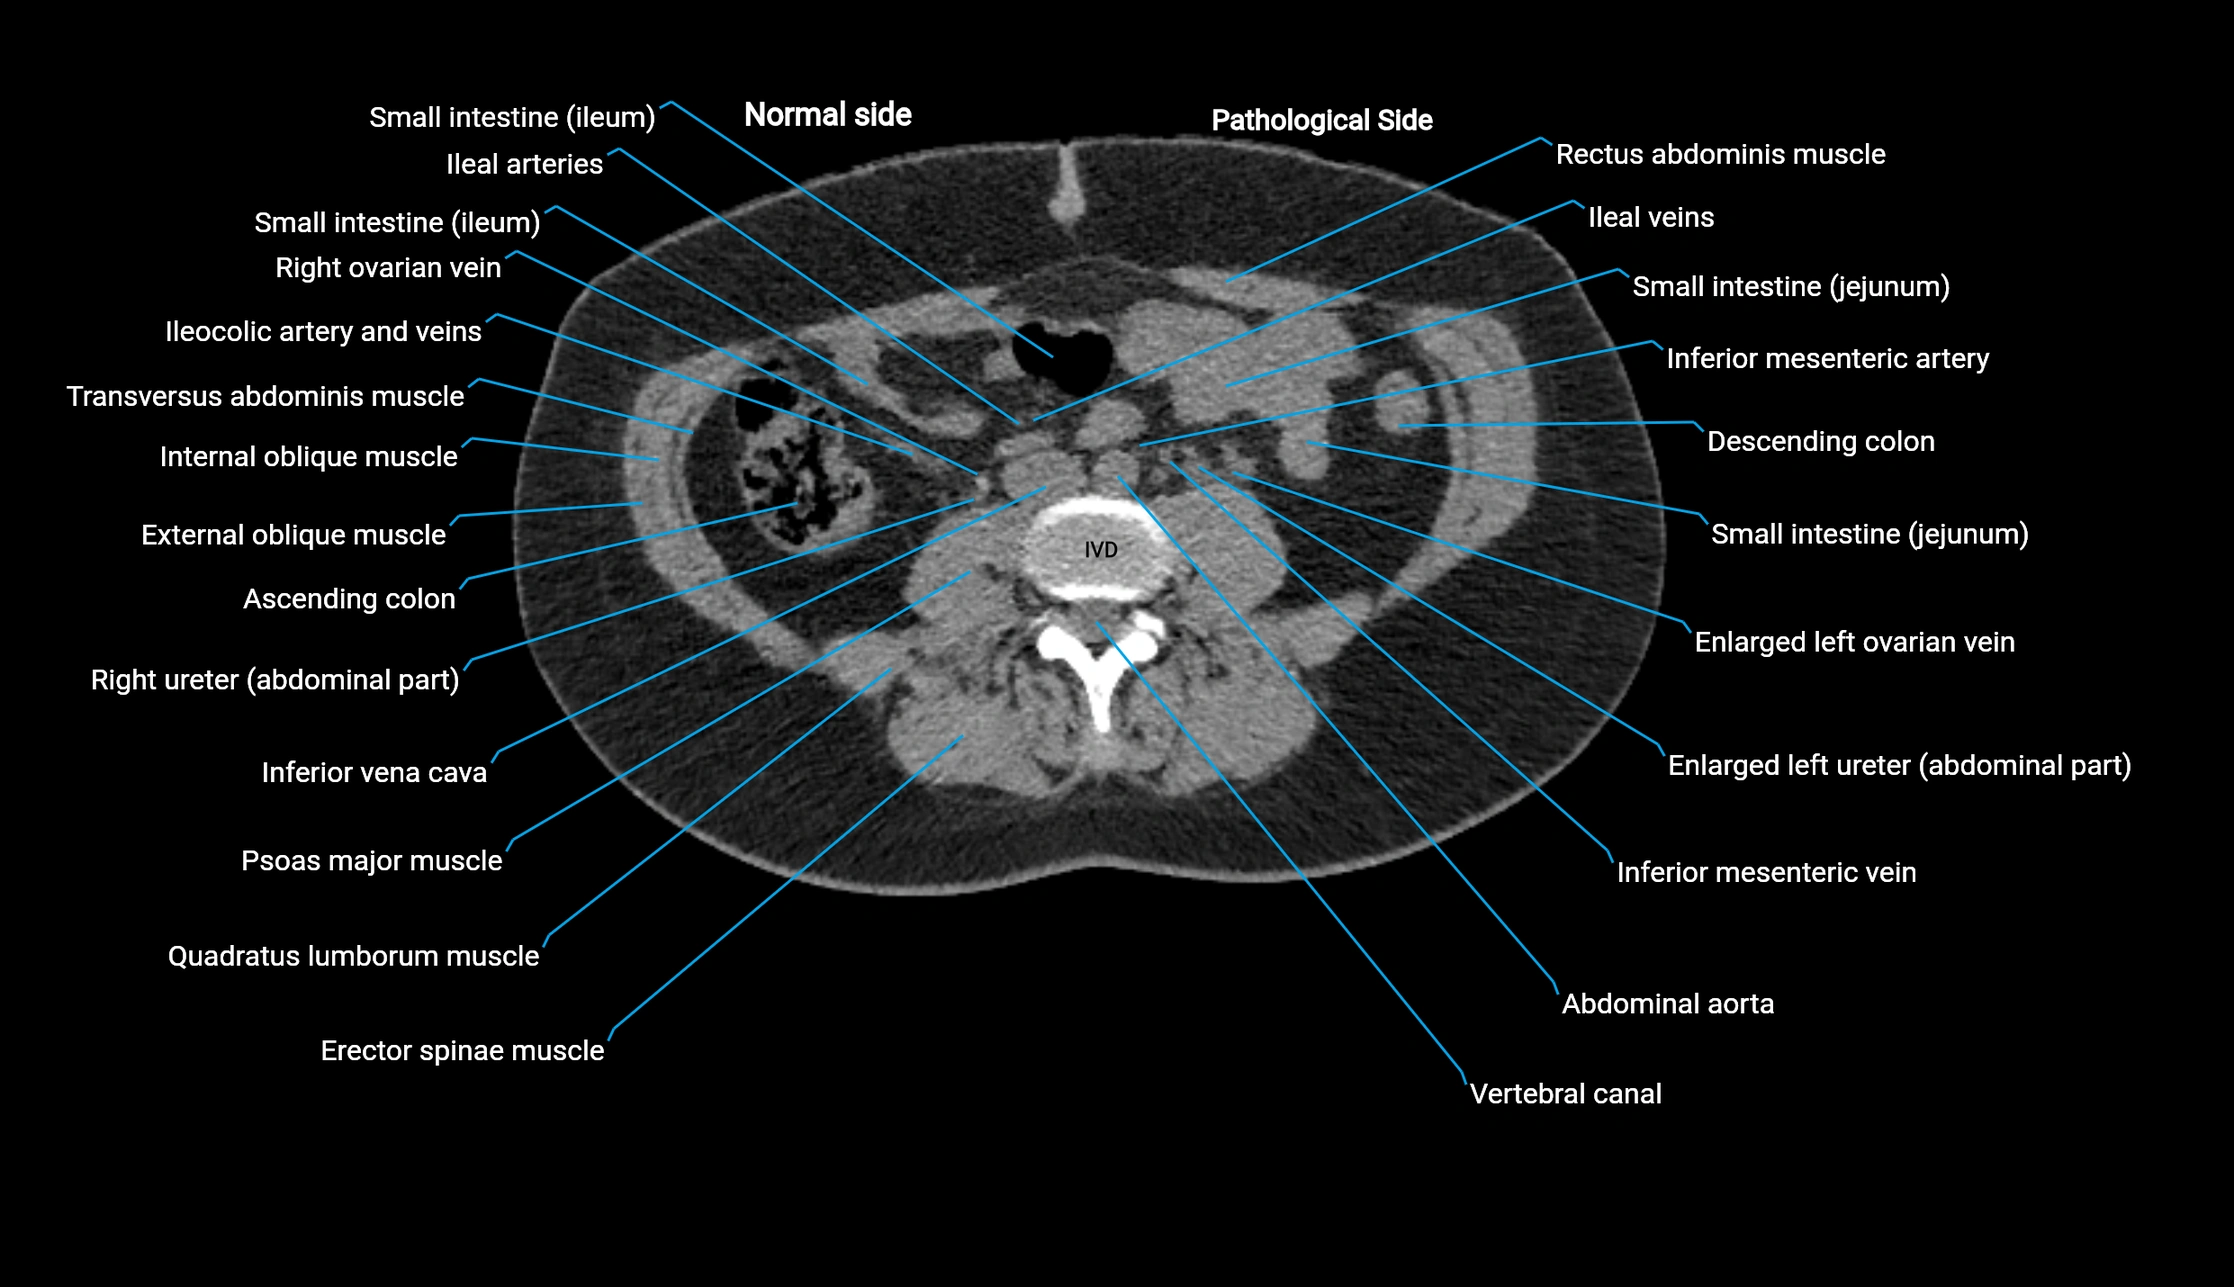

CT image

image